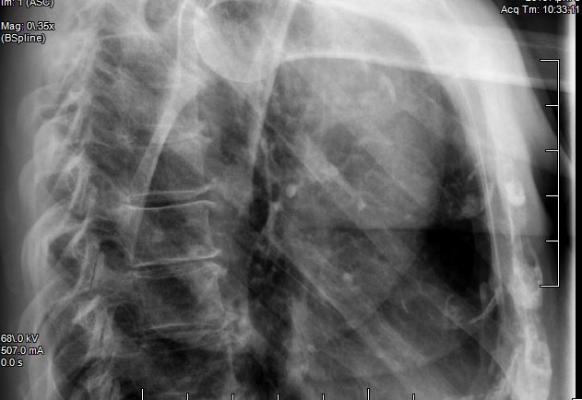

Every day we are exposed to various sources of ionizing radiation, including natural radiation in soil and rock, and important medical procedures like CT scans and X-rays.

Low doses of radiation, such as the exposure from medical imaging, are considered safe as they cause little DNA damage and apparently minimal effect on long-term health. Until now, other effects of exposure to low levels of radiation have remained hidden, meaning understanding the true risk associated with low doses of radiation has been difficult.

Prof. Phil Jones, lead author from the Wellcome Sanger Institute and MRC Cancer Unit, University of Cambridge, said: "Medical imaging procedures using radiation, such as CT scans and X-rays, have a very low level of risk — so low that it's hard to measure. This research is helping us understand more about the effects of low doses of radiation and the risks it may carry. More research is needed to understand the effects in people."